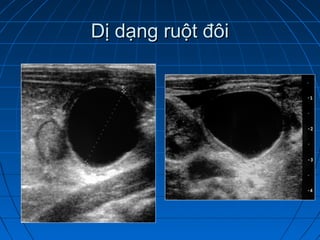

Dị dạng ruột đôiDị dạng ruột đôi

 Dị dạng hiếm gặp của ống tiêu hoáDị dạng hiếm gặp của ống tiêu hoá

 Có thể gặp ở tất cả các đọan , nhưngCó thể gặp ở tất cả các đọan , nhưng

hay gặp nhất là hồi tràng và thựchay gặp nhất là hồi tràng và thực

quảnquản

 Khối dạng dịch, dịch hồi âm hoặcKhối dạng dịch, dịch hồi âm hoặc

trống âmtrống âm

 Có thành mang cấu trúc lớp tương tựCó thành mang cấu trúc lớp tương tự

ống tiêu hoá,ống tiêu hoá,

 Thành liên tục với ống tiêu hóa kếThành liên tục với ống tiêu hóa kế

cận , có thể có nhu độngcận , có thể có nhu động

 Có thể thông hoặc không thông vớiCó thể thông hoặc không thông với

ống tiêu hoá ( chụp cản quang)ống tiêu hoá ( chụp cản quang)